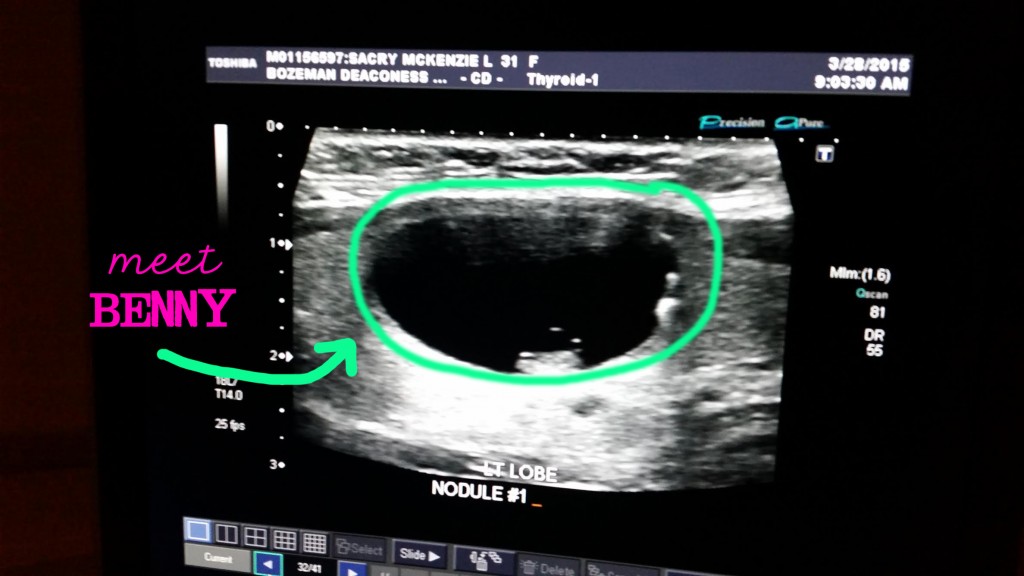

yep. that’s him. his name is benny. i thought he lived on the right side of my thyroid because that’s where it hurts. he doesn’t. i thought wrong. he actually lives on the band. or the “body. – the space in the middle of the “wings.”

you can pretty clearly see benny’s borders. (it’s the circled green outline courtesy of yours truly). duh. LOL. the black part of benny is fluid. the fact that benny is primarily fluid means he is most likely a cyst. ::confetti::

however – you’ll notice that bastard has a little solid bean of mass at the bottom and also a couple/few smaller spots on the right side. see it? yep. mother eff. that knocks him out of the “simple cyst” category and into the “moderate and/or complex” category. basically – this means he’ll likely need surgery to remove because they can’t suck him out with a hollow needle (::puke::) and poof his butt be gone. no, no, no. benny is a bit of a fighter. whatevs. as long as he isn’t cancer.

benny also lives pretty much directly over my trachea. (that’s my windpipe). and is the most likely suspect as to why i’ve been having such a difficult time breathing as of late.